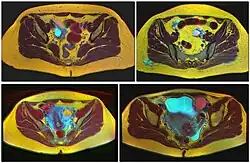

Ovarian cysts are usually diagnosed by pelvic ultrasound, CT scan, or MRI, and correlated with clinical presentation and endocrinologic tests as appropriate.[15] Ultrasound is the most important imaging modality, as abnormalities seen in a CT scan sometimes prove to be normal in ultrasound.[5][8] If a different modality is needed, then MRIs are more reliable than CT scans.[5]

Larger bilateral cysts can develop as a result of fertility treatment due to elevated levels of HCG, as can be seen with the use of clomifene for follicular induction, in extreme cases resulting in a condition known as ovarian hyperstimulation syndrome.[20] Certain malignancies can mimic the effects of clomifene on the ovaries, also due to increased HCG, in particular gestational trophoblastic disease. Ovarian hyperstimulation occurs more often with invasive moles and choriocarcinoma than complete molar pregnancies.[21]